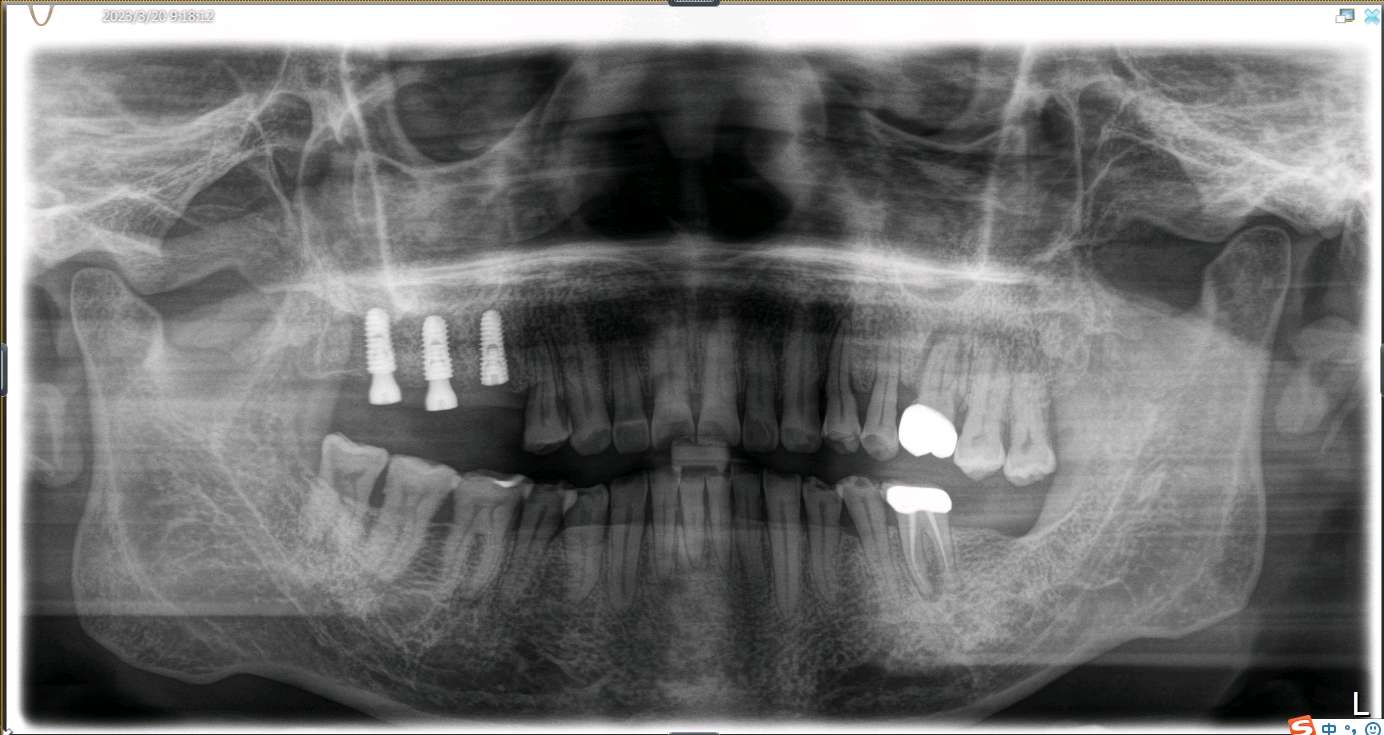

患者男,五十岁,右上后牙缺失一年。治疗计划拔出后种植修复。综合考虑患者自愿选择欧美hiossen种植体。最终15植入hiossen种植体4.5*11.5mm;16、17植入hiossen种植体5.0*10mm。二期三期如期进行。余近日戴牙。